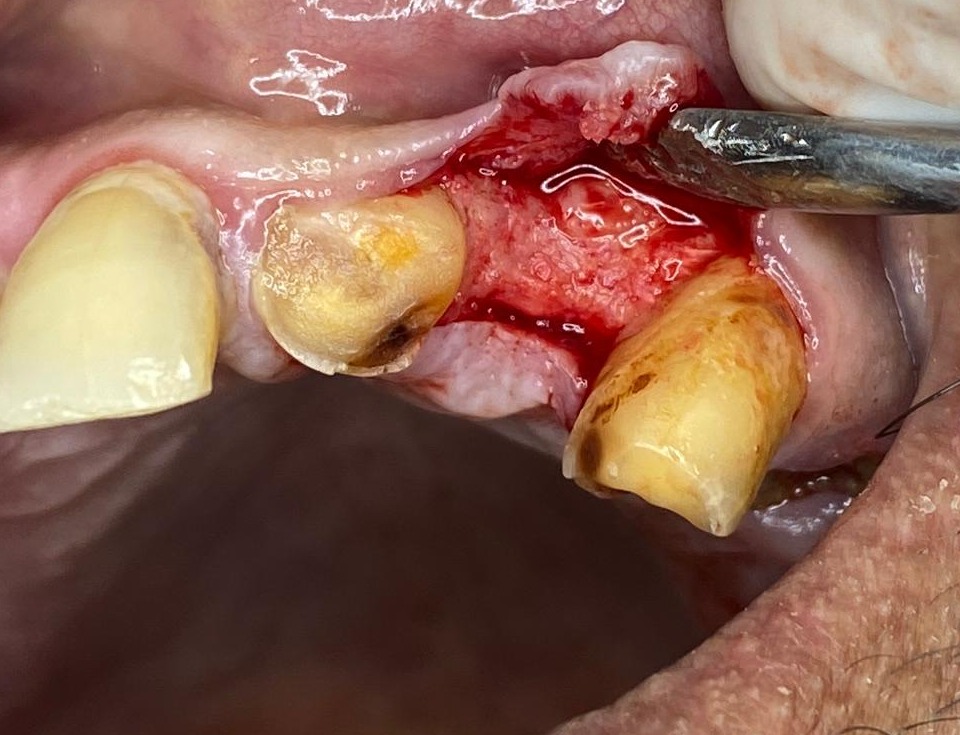

I used the machine today for extracting upper root piece it was a very good experience.

Usually with upper 4 rc treated root piece extraction can be stressful as the root piece keep breaking or crumbling and there is no grip for the root forcep. But with this extraction periotome tip it was really easy n no stress at all. I used elevator absolutely at the end as u can see it was hassle free n minimum bleeding .

Patient was very comfortable